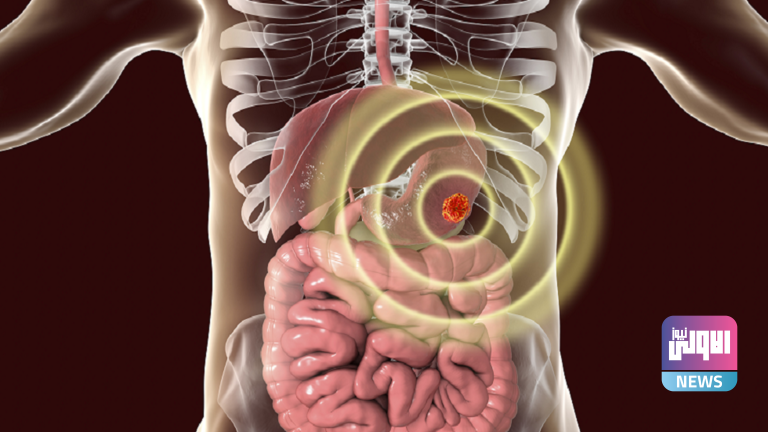

يصعب علاج السرطان بمجرد انتشاره، لذا فإن الاكتشاف المبكر هو المفتاح. والأفضل من ذلك، يمكنك تعديل خطر الإصابة بالمرض المميت في المقام الأول.وتنمو الخلايا السرطانية وتتكاثر بسرعة في الجسم، مما يجعل الجهود المبذولة لمنعها غير مجدية. وبطبيعة الحال، الوقاية خير من العلاج. وعلى الرغم من عدم وجود طريقة للوقاية من السرطان أو علاجه، إلا أنه يمكنك تعديل مخاطر إصابتك.ويوجه الباحثون انتباههم بشكل متزايد إلى الدور الذي تلعبه مكونات غذائية معينة في التأثير على مخاطر الإصابة بالسرطان. وواحدة من أكثر الارتباطات إثارة للدهشة تم رسمها بين تناول الخضروات المخللة وخطر الإصابة بسرطان المعدة. والخضار المخللة هي تلك المنتجات التي يتم تحضيرها بواسطة حمض صالح للأكل يضاف أو يتشكل عن طريق التخمير ويرجع الحفظ، جزئيا على الأقل، إلى وجود هذا الحمض.وكتب باحثون في مجلة Cancers التي راجعها الزملاء اقترحت زيادة خطر الإصابة بسرطان المعدة بسبب تناول الخضروات المخللة والأسماك المملحة، ومع ذلك فإن عدم وجود ارتباط بين الجرعة والاستجابة يستدعي إجراء تحليل كمي.كما أن العلاقة بين الجرعة والاستجابة هي علاقة ترتبط فيها مستويات التعرض المتزايدة إما بزيادة أو انخفاض مخاطر النتيجة. وفي هذه الحالة، تكون النتيجة زيادة خطر الإصابة بالسرطان.وحقق الباحثون في ارتباط تناول الخضار المخلل والأسماك المملحة بسرطان المعدة في دراسة الوبائيات الجينوم الكوري ودراسة السرطان متعددة المراكز الكورية.وكتبوا في هذا التحليل التلوي المنهجي للدراسات المستقبلية، وجدنا ارتباطا مهما بين زيادة مخاطر الإصابة بسرطان المعدة وزيادة تناول الخضروات المخللةولاحظ الباحثون أن معدل الإصابة بسرطان المعدة كان أعلى بمقدار 1.15 مرة مقابل زيادة قدرها 40 غم/يوم في تناول الخضروات المخللة وأعلى بمقدار 1.24 مرة، مقارنة بأعلى معدل مع أقل تناول.وخلص الباحثون إلى أن “نتيجة التحليل التلوي للجرعة والاستجابة التي أجريناها تعزز التحليلات التلوية السابقة، والتي أظهرت زيادة خطر الإصابة بسرطان المعدة ، مقارنة بين أعلى وأقل تناول للخضروات المخللة والأسماك المملحة. والنتائج التي توصلنا إليها تدعم الدليل على أن تناول كميات كبيرة من الخضار المخلل والأسماك المملحة يرتبط بارتفاع مخاطر الإصابة بسرطان المعدة